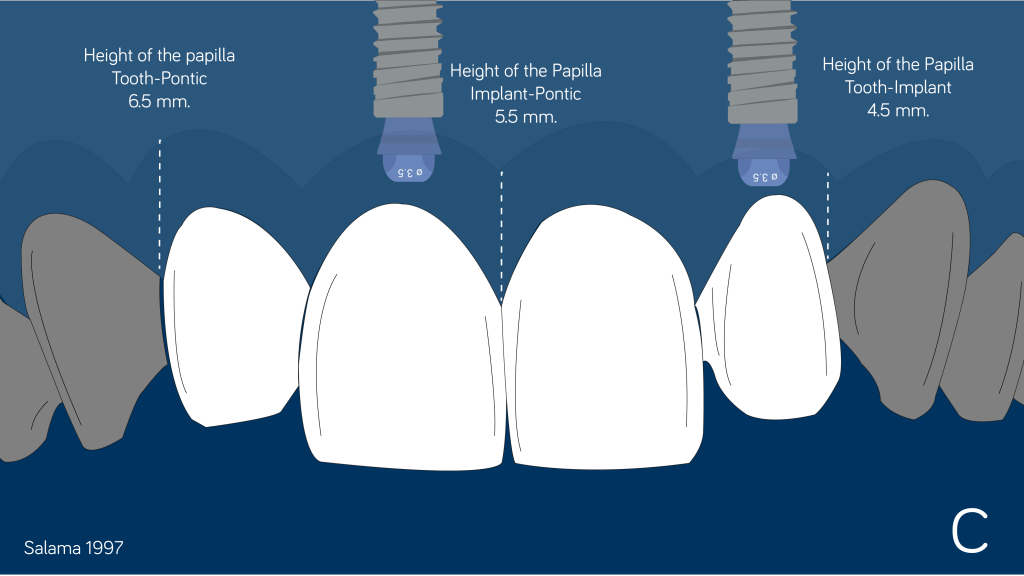

做这个选择时总是要记住龈乳头在不同解剖和修复要素之间的预期高度(Salama 1997)。

龈乳头高度(Maurice Salama 1997年发表的文章指出)

使用窄径基台(3.5mm)有助于避免邻面乳头的侵犯。如果决定将种植体植入到侧切牙间隙,这种窄基台会更有用。